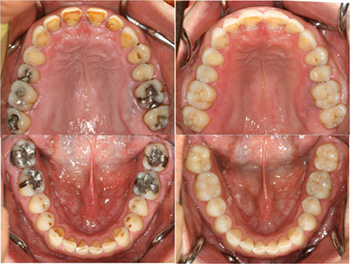

さてさてどこを治したでしょうか!?

奥歯のレジン治療です。

答え、

答え

奥歯4本の治療を行いました。

7番 レジン治療

6番 ハイブリットアンレー

5番 ハイブリットインレー

4番 レジン治療

4本治療したと分かった人・・・

プロ以上の目をお持ちで^^;

因みに私は自分で詰めた4番(奥から4番目の歯)

後日見たら本物の歯だと。。。